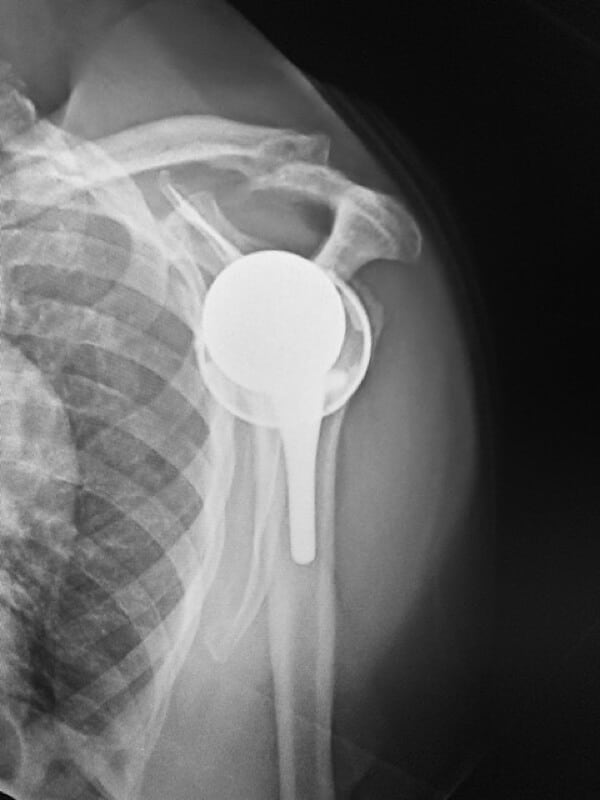

Shoulder Innovations, InSet